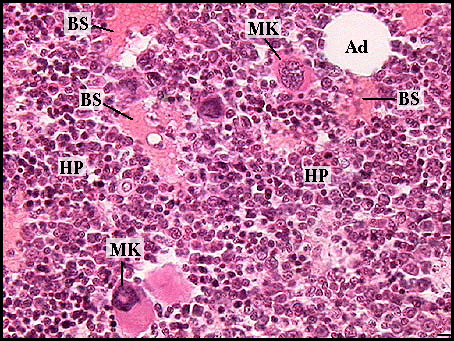

Escribe 2 estructuras de la siguiente muestra

Escoge una o varias respuestas

Identifique las estructuras de la imagen (son 5, escriba con letra minúscula)

Respuesta escrita